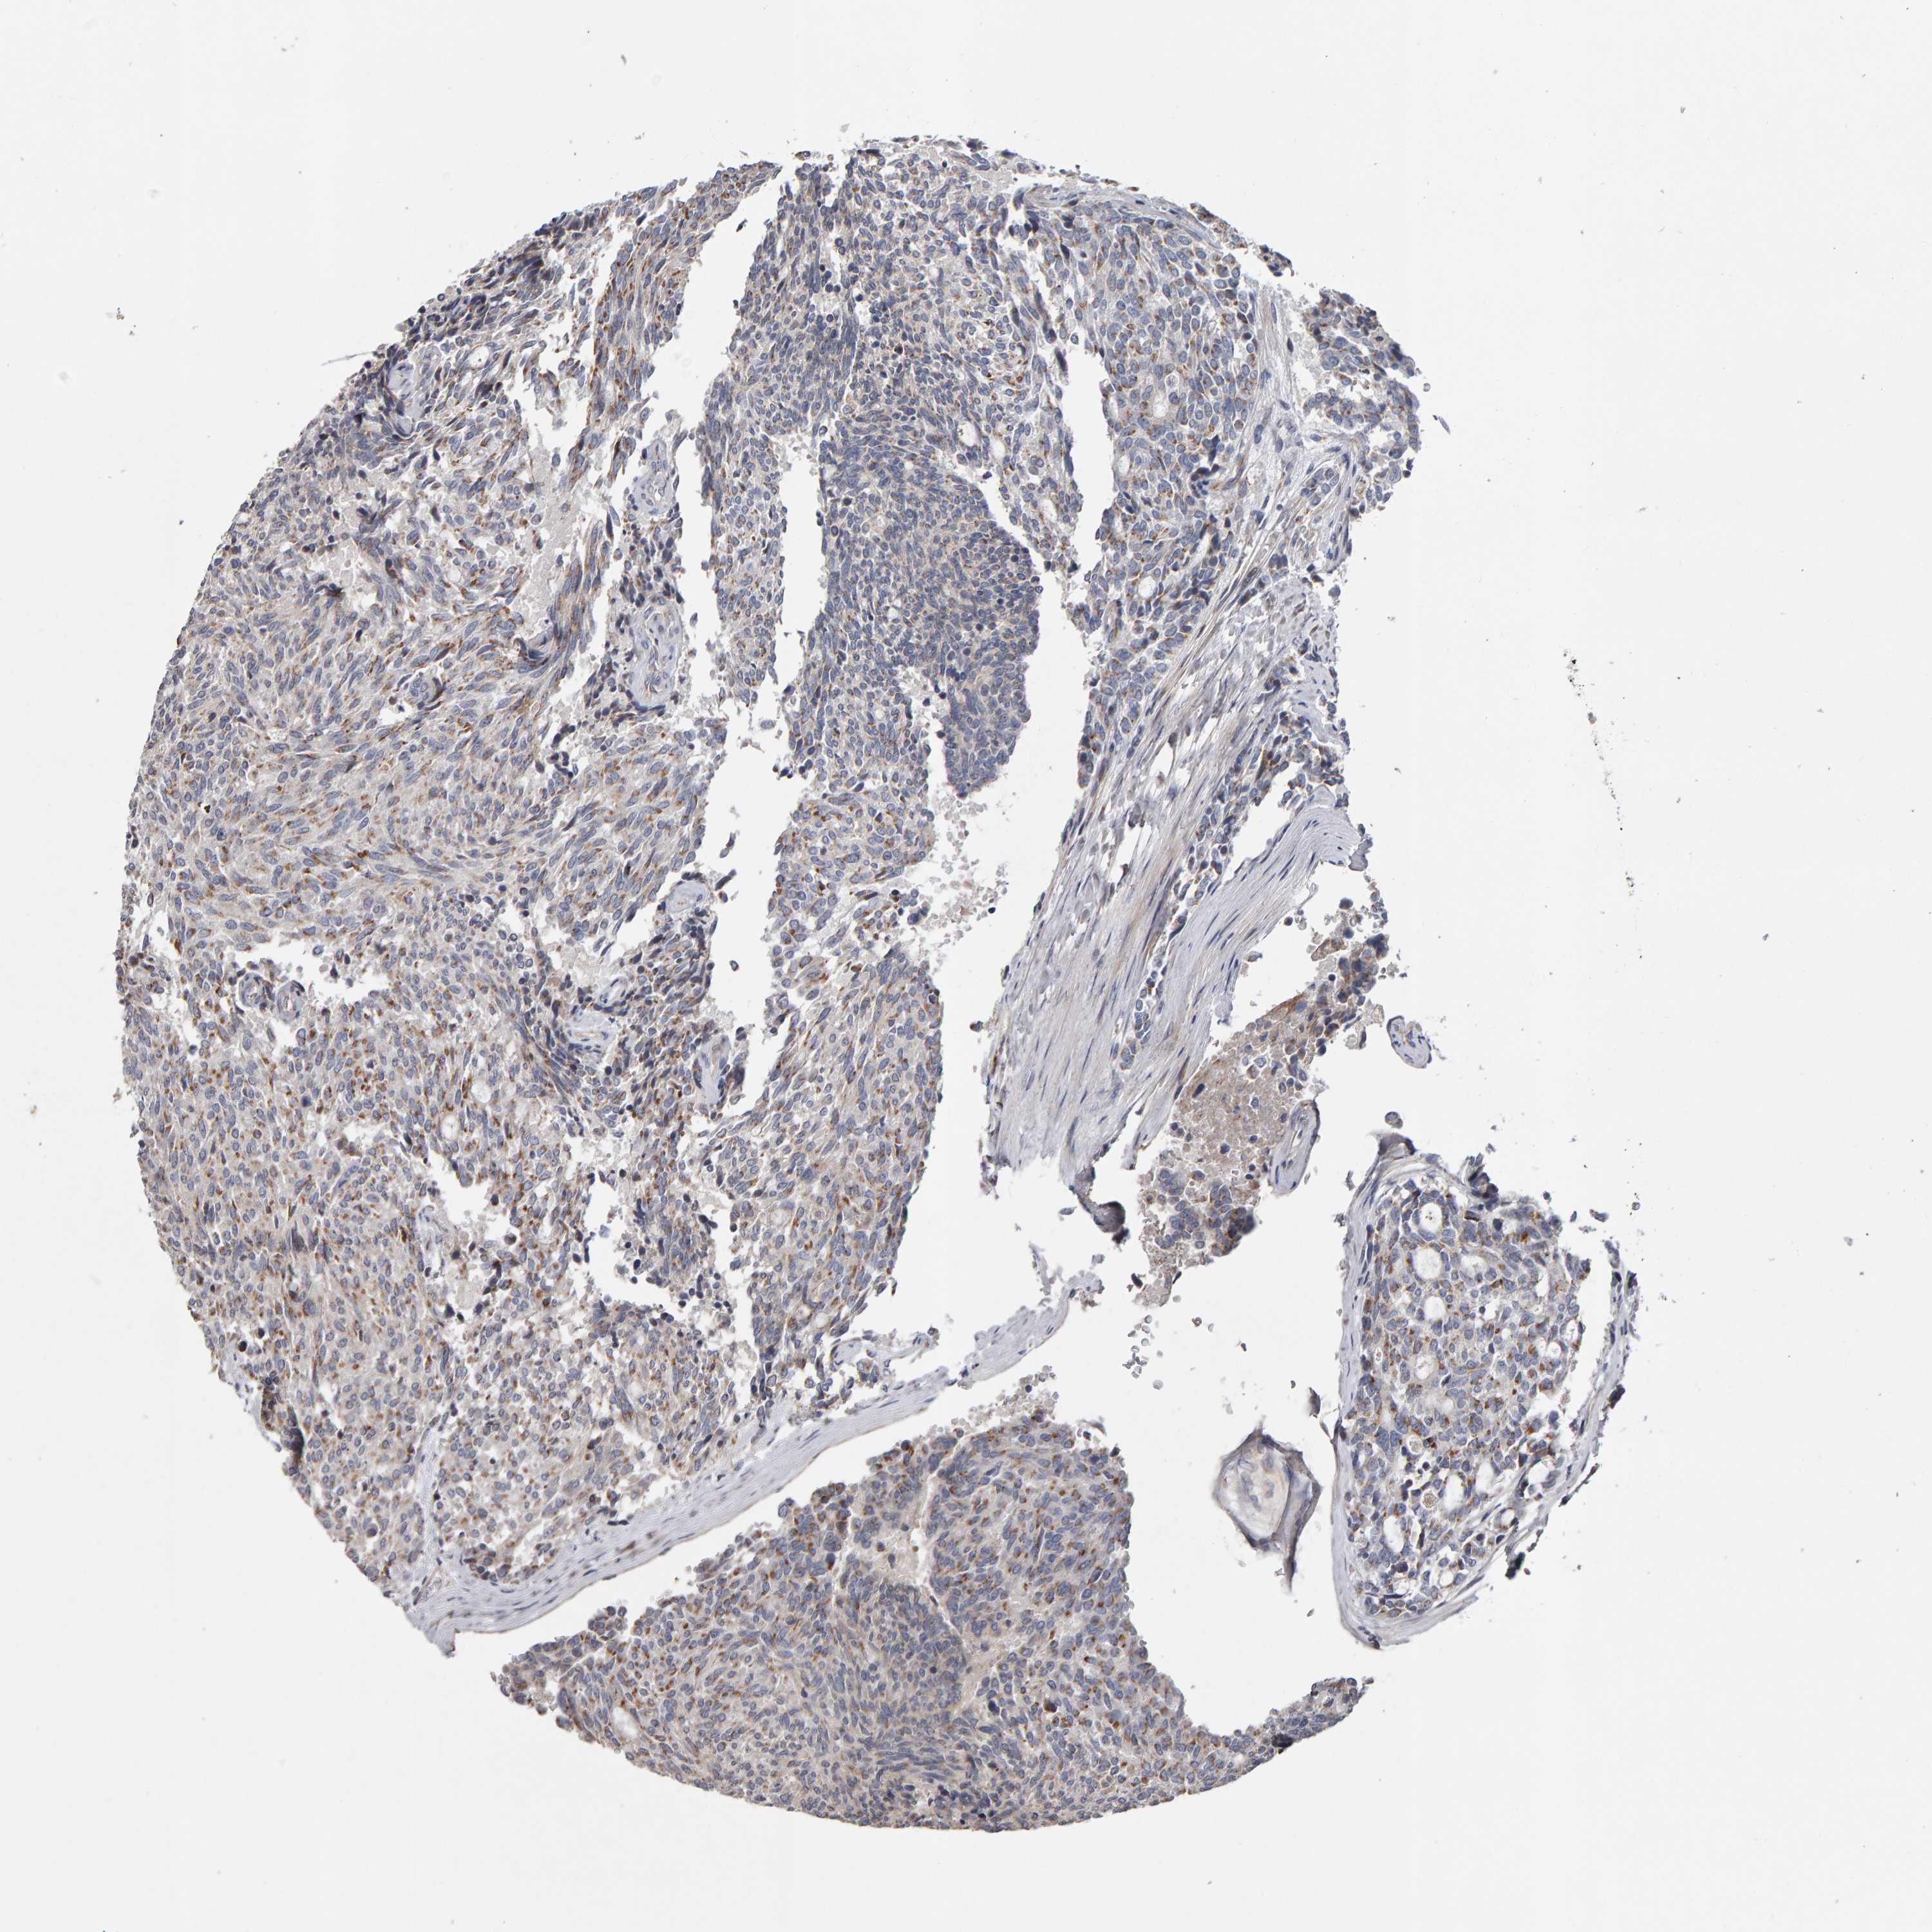

CANT1